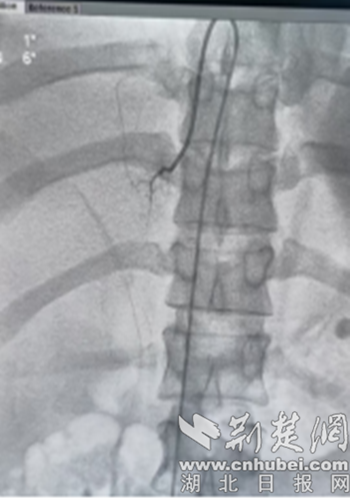

CT。通訊員 供圖

該技術采用微創介入技術,通過股靜脈,對雙側腎上腺中心靜脈分段采血,直接、準確測定醛固酮、腎素等腎上腺激素局部水平。但由于腎上腺靜脈較為細小、解剖變異多,難度大,對操作者的介入技術要求高,需要非常豐富的介入手術技巧才能完成。

手術由沈俊博士、夏南博士、曾海星主治醫師組成介入團隊成功實施,過程順利,術后ARR證實患者為原發性醛固酮增多癥,患者雖然雙側腎上腺有結節,但是左側腎上腺醛固酮分泌為右側80倍,左側腎上腺為醛固酮分泌優勢側。下一步擬對左側腎上腺結節微創手術。